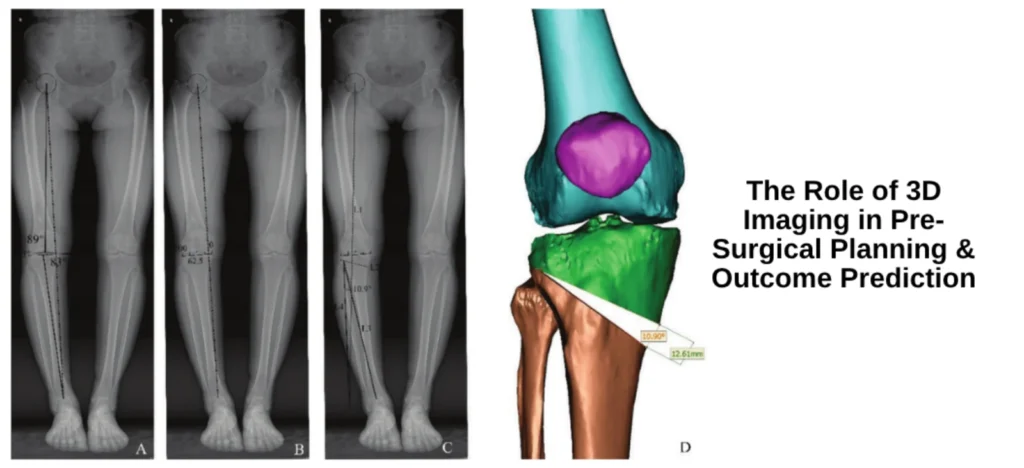

Advanced MRI, CT, or CBCT scans generate patient-specific 3D models of bones, ligaments, and joints.

These models allow surgeons to simulate bone cuts, joint alignment, implant sizing, and surgical steps even before surgery begins.

Pinpoint accuracy in fracture fixation, deformity correction, and implant placement.